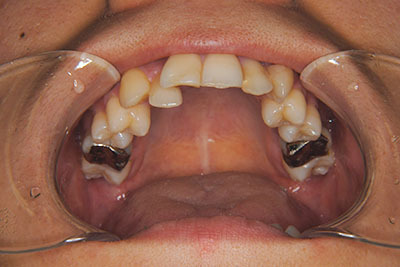

おとなの方でも矯正治療をあきらめないでください!

いくら歯が動き易くとも、本人がやる気でなければ効果は出ませんし、むし歯発生のリスクも高まります。おとなの方は顎の成長が終わっているため、治療の計画が立てやすいとも言えます。「もう大人だから…」とあきらめず、一度ご相談ください。